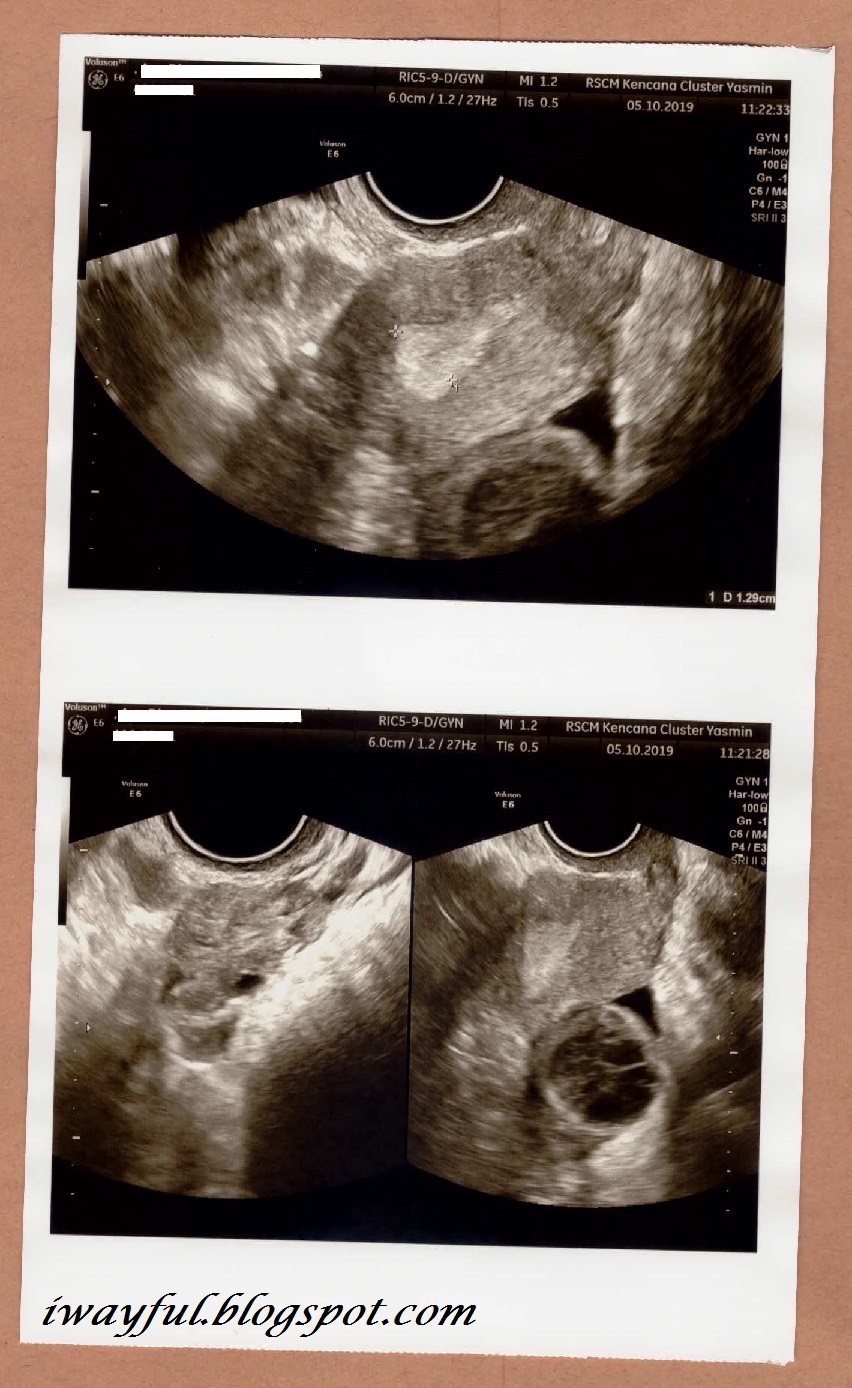

Jam 11 lewat kami dipanggil masuk ruang konsultasi, istri di-USG terlihat ada satu telur yang belum pecah. Setelah USG, istri dimasukkan obat Tramal (suppository 100 mg) lewat anus untuk mengurangi rasa nyeri, lalu dimulailah tindakan Endometrial Scratching sekitar 15 menitan.